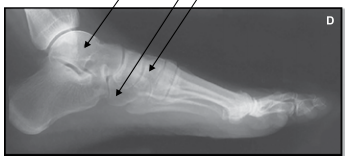

Observe a imagem de um exame mediolateral do pé e assinale a alternativa correta.